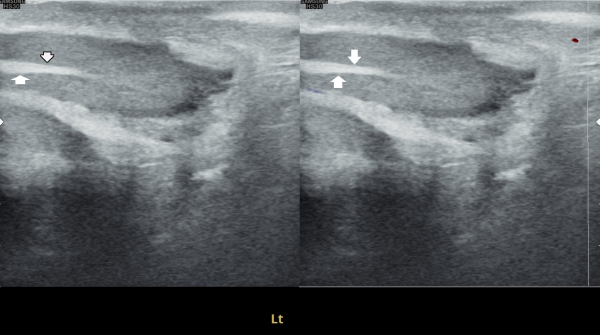

주2회 전립선의 표적 치료후 고환의 미석증이 줄어 들고 있는 경직장 전립선 초음파 검사 사진

Transrectal ultrasound image showing a reduction in testicular microlithiasis after twice-weekly targeted prostate treatment.

전립선의 표적치료후 고환의 미석증이 없어지고 고환이 커진 경직장 전립선 초음파 자료 입니다.(주2회 표적치료)

This is a transrectal ultrasound image showing the improvement after targeted prostate treatment.

After twice-weekly targeted treatment, testicular microlithiasis disappeared, and the testicles increased in size.

The ultrasound image on the left shows the initial examination, where testicular microlithiasis (tiny calcifications) was present.

The ultrasound image on the right is a follow-up study after several months of targeted therapy to the vas deferens, ejaculatory ducts, seminal vesicles, and prostate, twice a week.

The follow-up scan demonstrates that the previously noted microlithiasis has improved, suggesting that the targeted treatment contributed to the restoration of testicular health.